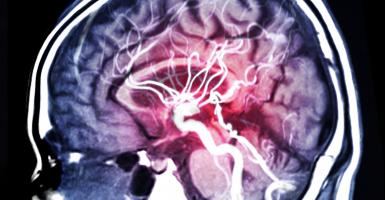

La maladie de Parkinson est la 2è maladie neurodégénérative la plus répandue dans le monde après la maladie d’Alzheimer. C’est une maladie restée jusque-là incurable et dont seuls les symptômes peuvent être soulagés. Aux premiers stades, les médicaments peuvent apporter ce soulagement, mais alors que la maladie progresse, cela ne suffit plus. Les patients, leurs familles et les médecins peuvent alors opter pour des thérapies plus invasives jusqu’aux interventions sur le cerveau.

Parmi ces traitements plus invasifs, figure la stimulation cérébrale profonde, qui nécessite que des électrodes soient implantées dans le cerveau. La technologie, plus récente, permet la perfusion automatisée de médicaments directement dans les intestins via un tube ou dans la paroi abdominale. Mais même ces traitements avancés n’aboutissent pas toujours aux résultats souhaités ou perdent de leur efficacité avec le temps.